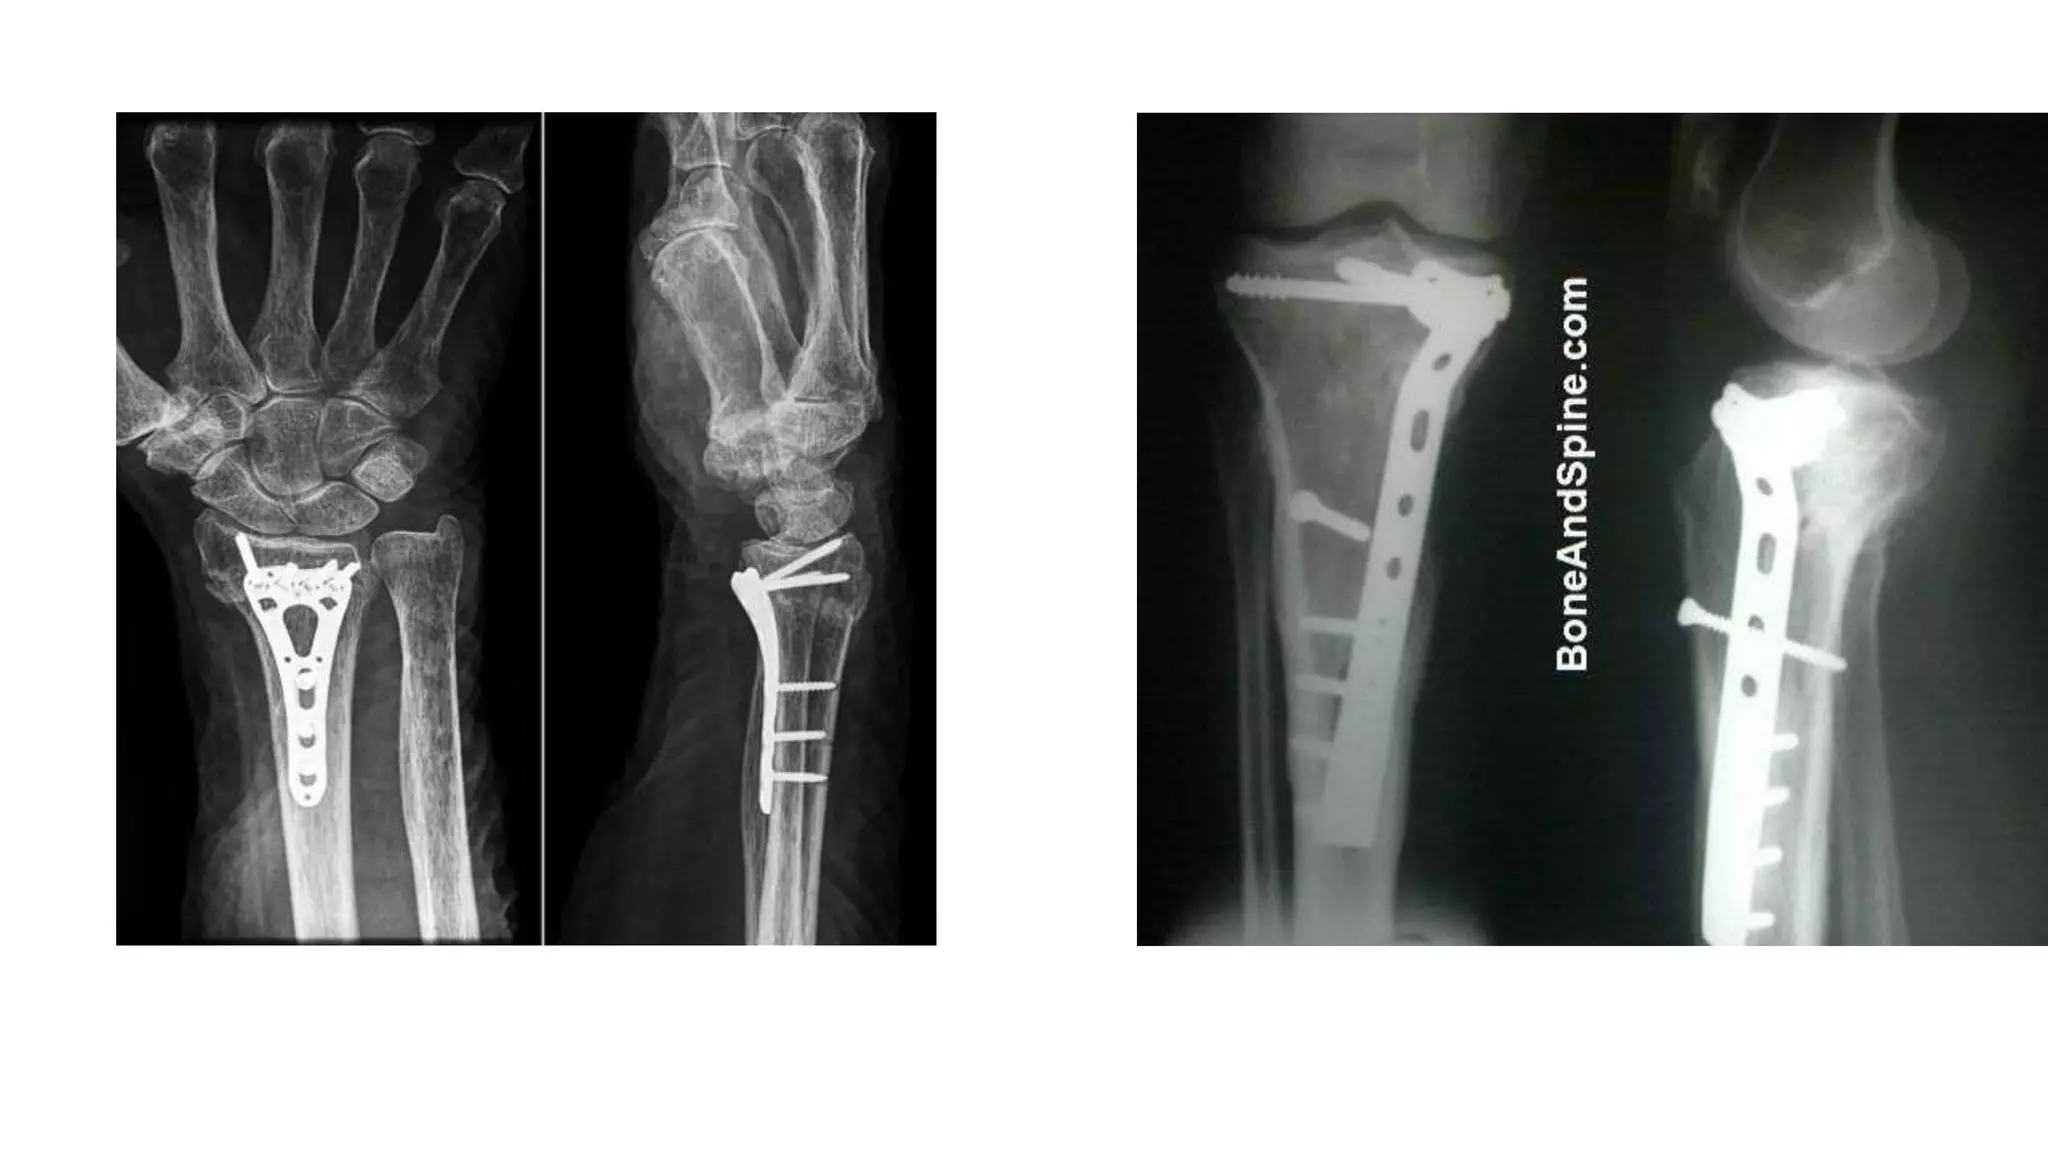

Buttress plate

 It supports weakened area of cortex.

 It prevents bone from collapsing during healing process, facilitating a

wider distribution of load.

 use- epiphyseal and metaphyseal fracture( distal radius , tibial plateau)

Buttress plate  Itsupports weakened area of cortex.  It prevents bone from collapsing during healing process, facilitating a wider distribution of load.  use- epiphyseal and metaphyseal fracture( distal radius , tibial plateau)